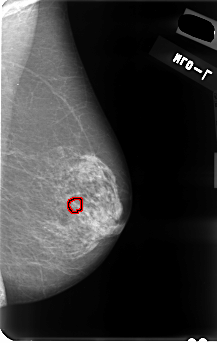

B_3037_1.LEFT_CC

LEFT_CC LINES 4768 PIXELS_PER_LINE 3120 BITS_PER_PIXEL 12 RESOLUTION 50 OVERLAY

FILE: B_3037_1.LEFT_CC.OVERLAY

TOTAL_ABNORMALITIES 1

ABNORMALITY 1

LESION_TYPE CALCIFICATION TYPE PUNCTATE-PLEOMORPHIC DISTRIBUTION CLUSTERED

ASSESSMENT 4

SUBTLETY 3

PATHOLOGY MALIGNANT

TOTAL_OUTLINES 1

BOUNDARY